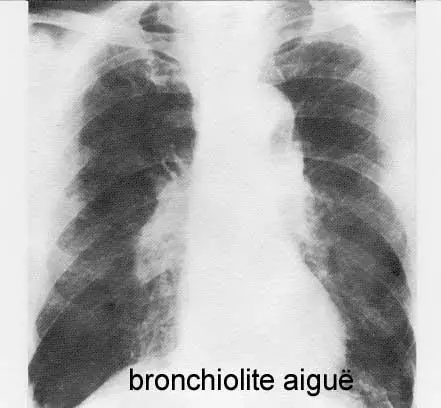

Prise en charge des BRONCHIOLITES